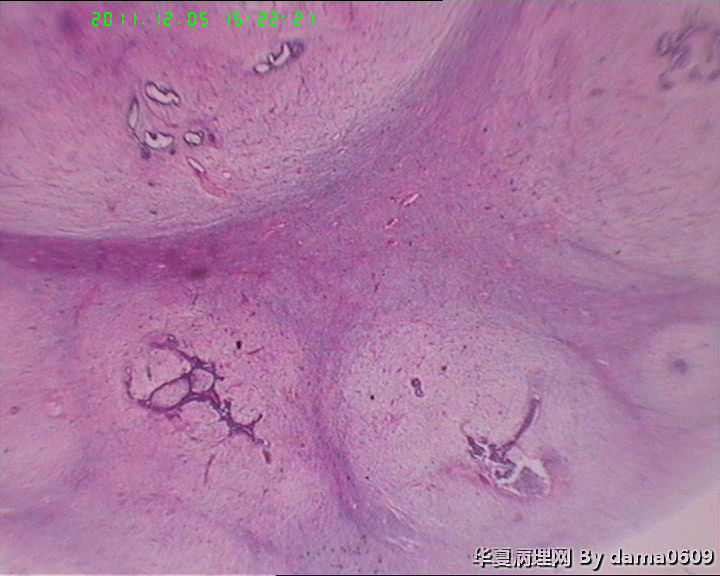

肿物一:镜下见乳腺小叶结构紊乱,小叶内、小叶间间质增生,构成肿瘤主质。增生间质呈梭形细胞样,细胞稀疏、异性不明显,其间见大量胶原纤维,小血管增生,局灶有红细胞渗出。见到一处导管大汗腺化生。

肿物二:镜下呈结节状,结节以导管或小叶为中心,围以增生的间质成分,梭形细胞构成,稀疏,增生的血管呈“鹿角状”。大结节内见局灶间质有出血或红细胞外渗,局灶导管内间质增生呈乳头/分叶状,上皮下无密集增生的间质细胞。结节大小不等,以窄带样纤维细胞束彼此分隔,互不融合,纤维细胞束细胞密集,内有增生的小血管。